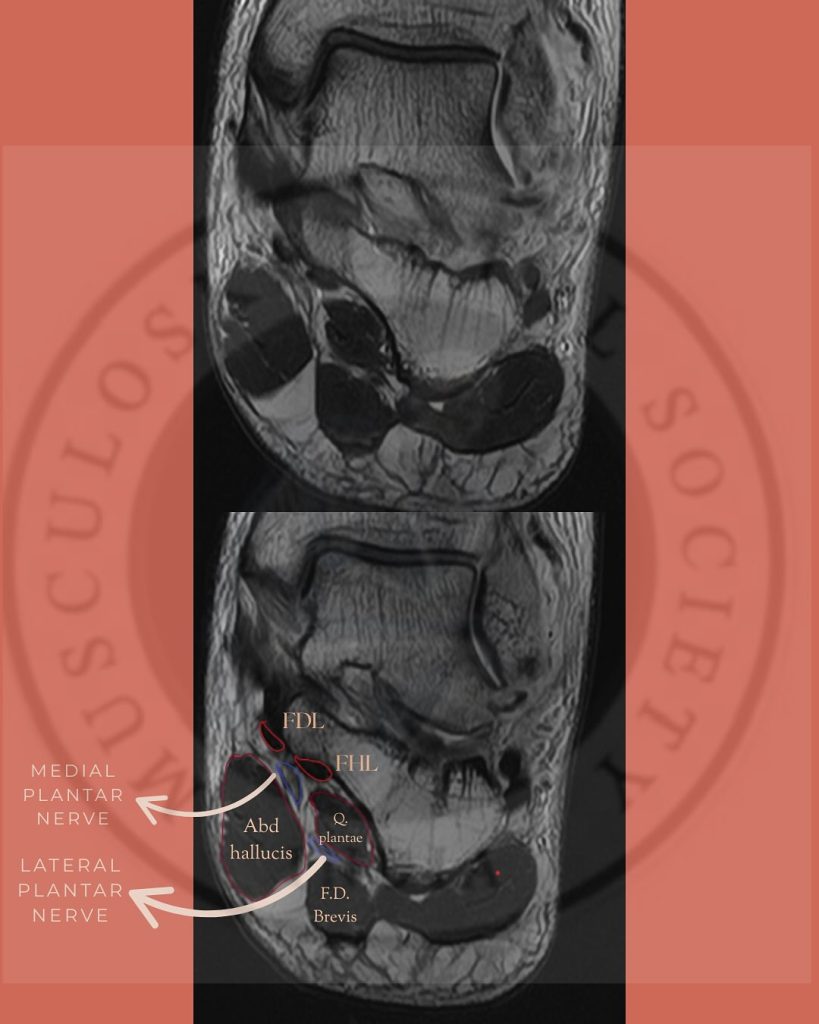

Пальпация медиального подошвенного нерва (MPN)

Анатомическое расположение:

Медиальный подошвенный нерв является ветвью большеберцового нерва и проходит по медиальной части подошвы стопы. Наиболее частой зоной его компрессии является область бугристости ладьевидной кости, где нерв проходит в узком фиброзно-мышечном туннеле между ладьевидной костью и мышцей, отводящей большой палец стопы [18]. В этой зоне нерв уязвим к механическому сдавлению, особенно при повышенной пронации стопы или гипертрофии мягких тканей.

Пальпация нижнего пяточного нерва (ICN)

Нижний пяточный нерв (первая ветвь латерального подошвенного нерва) отходит вблизи бифуркации большеберцового нерва и проходит медиально и кпереди от бугристости пяточной кости [21]. Он иннервирует надкостницу пяточной кости, подошвенные связки и ряд внутренних мышц стопы. Компрессия нерва часто возникает в пространстве между фасцией мышцы, отводящей большой палец, и квадратной подошвенной мышцей.